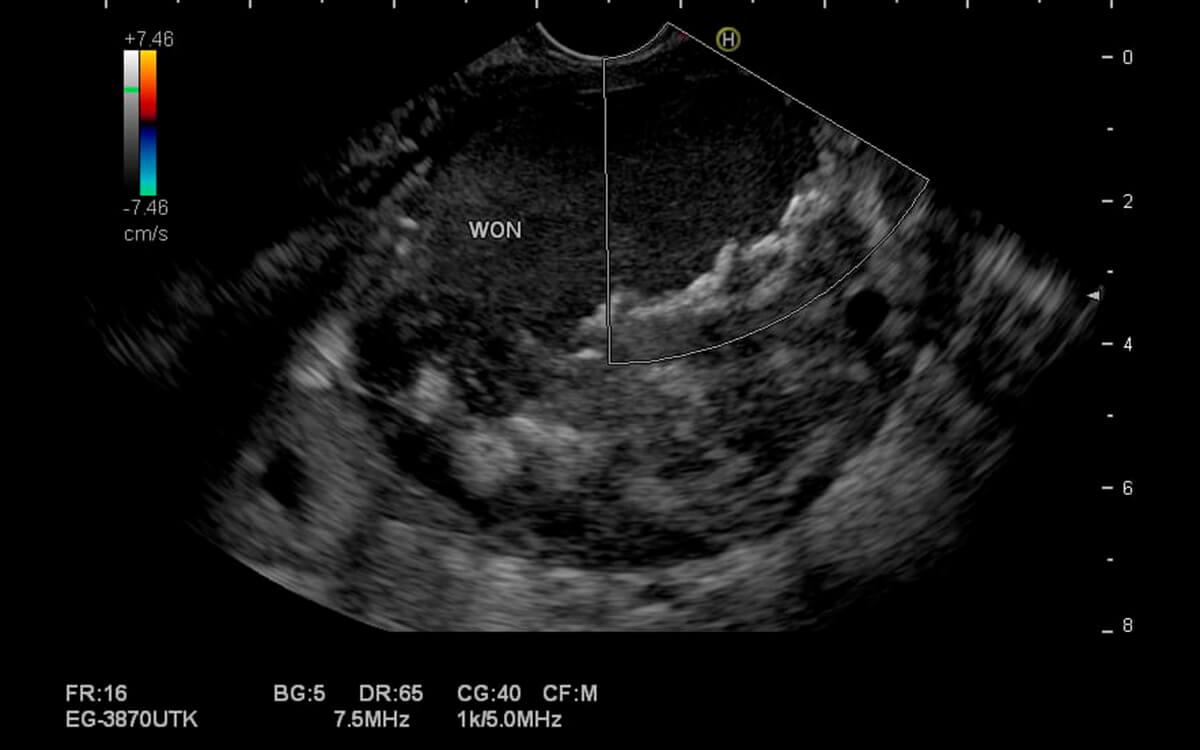

A Ecoendoscopia Pancreatica , é um exame diagnóstico e potencialmente terapêutico do trato digestivo alto e baixo. O médico endoscopista pode analisar o esôfago, estômago, duodeno, pâncreas, vias biliares, vesícula biliar, fígado, intestino (cólon) e reto com um ultrassom, através de acesso por endoscopia (ecoendoscopia alta) ou colonoscopia (ecoendoscopia baixa).

O Dr. Hugo Guedes, médico especialista em Ecoendoscopia Pancreatica pela USP e do Hospital Sírio Libanês, explica que "a ecoendoscopia possibilita examinar camadas mais profundas dos órgãos digestivos, que não poderiam ser avaliadas apenas pela endoscopia comum, pois esta permite apenas a visualização superficial de suas paredes internas".

Ecoendoscopia Pancreatica faz o exame ultrassonográfico do aparelho digestivo, além de permitir a realização de punção por agulha diretamente desses órgãos (ecoendoscopia com biópsia). Dessa forma, podemos analisar diversas doenças do trato digestivo, como: